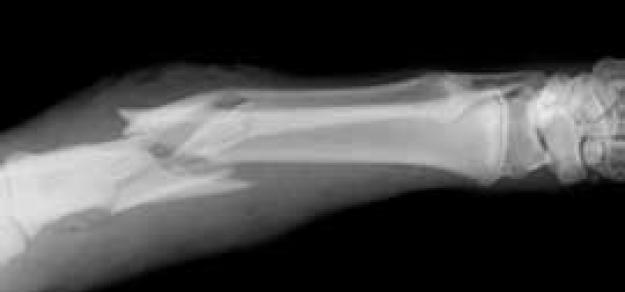

The Lancet Diabetes & Endocrinology, 4 de octubre de 2018 Los hallazgos sugieren que la suplementación con vitamina D no previene fracturas o caídas, ni tiene efectos clínicamente significativos en la densidad mineral ósea. No hay diferencias entre los efectos de dosis más altas y más bajas de vitamina D. Hay poca justificación para usar suplementos de vitamina D para mantener o mejorar la salud musculoesquelética. Esta conclusión debe reflejarse en las guías clínicas.

BMJ, 29 de agosto de 2018 El metaanálisis identifica 15 determinantes genéticos de la fractura, que todos también influyen en la densidad mineral ósea. Entre los factores de riesgo clínicos para la fractura evaluados, solo la densidad mineral ósea muestra un efecto causal importante en la fractura. La predisposición genética a niveles más bajos de vitamina D y la ingesta estimada de calcio de fuentes lácteas no se asocian con el riesgo de fracturas.